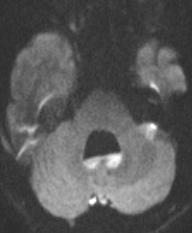

这个比较考眼力:DWI可见端倪, 箭头处为引流静脉。

脑发育性静脉畸形是最常见的脑血管畸形。常在CT、核磁检查时偶然发现。多数情况下为良性病程,个别情况下可伴临床症状,包括癫痫、局灶性神经功能障碍如运动感觉障碍、头痛、引起颅内出血相关症状等。可伴其他血管畸形,最常见的为海绵状血管瘤(12%-40%)。

典型征象:水母头征,由很多较细的髓静脉组成,这些髓静脉的血液汇入较粗的引流静脉。SWI和CT/MRI增强扫描尤为明显,其他核磁序列和CT平扫亦有可能显示。